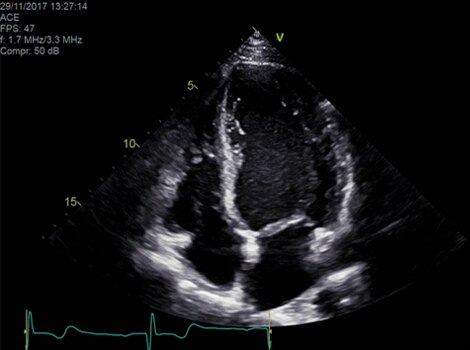

Cartera Vivid

El Doppler automático cardíaco proporciona automáticamente resultados de medición Doppler para los parámetros más comunes, con una mínima guía del usuario. Más información

Vivid E95

La tecnología cSound de formación de haces ofrece una calidad de visualización excepcional con una impresionante resolución en los formatos 2D, flujo de color, Doppler y 4D. Más información

Proporciona acceso instantáneo a vistas 4D predefinidas (de fábrica o por el usuario) durante el modo activo para proporcionar datos más uniformes a la vez que reduce el tiempo de exploración. Más información

Ecocardiógrafo de la línea VividTM con Automated Function Imaging (AFI)

Evalúa la función del ventrículo izquierdo y el rendimiento cardíaco con claridad, lo que mejora la confianza clínica.  Más información

Ecocardiógrafos de la línea Vivid

Vivid E95 con rendimiento cSound hace que la adquisición de imágenes 4D resulte tan sencilla como la de imágenes 2D para cuantificar el movimiento de la pared ventricular izquierda. Más información

Ecocardiógrafo de la línea Vivid™ con Automated Function Imaging (AFI)

Cuantificación automatizada de la fracción de eyección y el movimiento de la pared del ventrículo izquierdo.

Evaluación semiautomatizada de la válvula en 3D. Más información

Proporciona resultados de las mediciones Doppler para los parámetros más comunes, con mínima orientación al usuario. Más información

Ecocardiógrafos de la línea Vivid con cuantificación automatizada (EF)